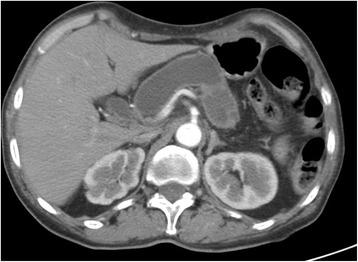

A 69-year-old woman was hospitalized in May 2016 for epigastric pain and weight loss. Her past medical history revealed an undefined main pancreatic duct dilation that was subsequently confirmed at CT scan (23 mm) and endoscopic ultrasound. There was no evidence of pancreatic masses, but the cephalic portion of the main pancreatic duct presented hypoechoic nodules. A diagnosis of the main-duct intraductal papillary mucinous neoplasm was made, and the patient underwent total pancreatectomy. Pathological examination showed a collision tumor constituted by a ductal adenocarcinoma involving the whole pancreas and a neuroendocrine tumor located in the duodenal peripancreatic wall and the head of the pancreas. There was one peripancreatic lymph node metastasis from the ductal adenocarcinoma and eight node metastases from the neuroendocrine tumor. These findings suggested a diagnosis of collision of neuroendocrine and ductal adenocarcinomas of the pancreas. The postoperative course was uneventful.

一名69岁女性于2016年5月因上腹部疼痛和体重减轻入院。她的既往病史显示有未明确的主胰管扩张,随后CT扫描(23毫米)和内镜超声证实了这一情况。没有胰腺肿块的证据,但主胰管头部出现低回声结节。诊断为主胰管内乳头状黏液性肿瘤,患者接受了全胰切除术。病理检查显示为碰撞瘤,由累及整个胰腺的导管腺癌和位于十二指肠胰周壁及胰头的神经内分泌肿瘤组成。导管腺癌有1个胰周淋巴结转移,神经内分泌肿瘤有8个淋巴结转移。这些发现提示胰腺神经内分泌癌与导管腺癌碰撞的诊断。术后过程顺利。